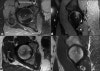

- MRI

대퇴골두와 경부에 걸쳐 부분적 또는 광범위하게 T1에서는 저신호 강도, T2 또는 지방 억제 영상에서는 고신호 강도로 나타나는 경계가 불명확한 이상소견을 보입니다(전형적인 골수 부종 소견).

연골하 골판 부위에 평행하게 주행하면서 T1에서는 저신호 강도, 다른 강조 영상에서는 다양한 신호 강도로 나타나는 이상 신호 강도선(연골하 골절선, MR crescent sign)을 관찰할 수 있습니다.

대부분 대퇴골두의 전상방에서 관찰되지만 일부에서는 후상방에서 관찰되기도 합니다.

골수 부종과 연골하 골절 소견은 대퇴골두 무혈성 괴사에서도 관찰되기 때문에 감별진단에 주의해야 합니다.

MRI : subchondral insufficiency fracture of the femoral head

MRI(Sagittal view) : Subchondral stress fracture of the femoral head